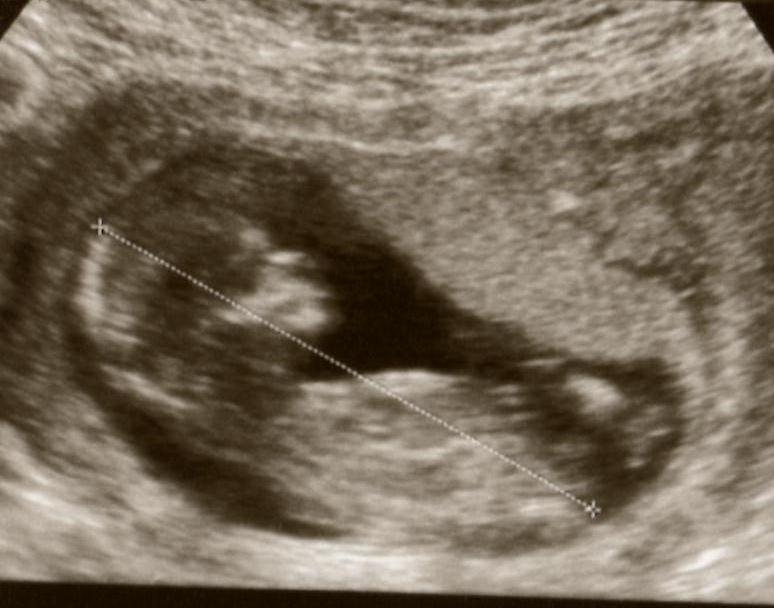

Hoping for a girl this time, was looking for some hope from my 12 week scan photo's?

I am not even sure if you can see a nub ... but any guesses would be much appreciated (I have also posted in the gender ultrasound section ... so apologies if you have looked twice)

If anyone can see a nub, could you please tell me where you are looking? Thanks so much ..

Attachment 2541